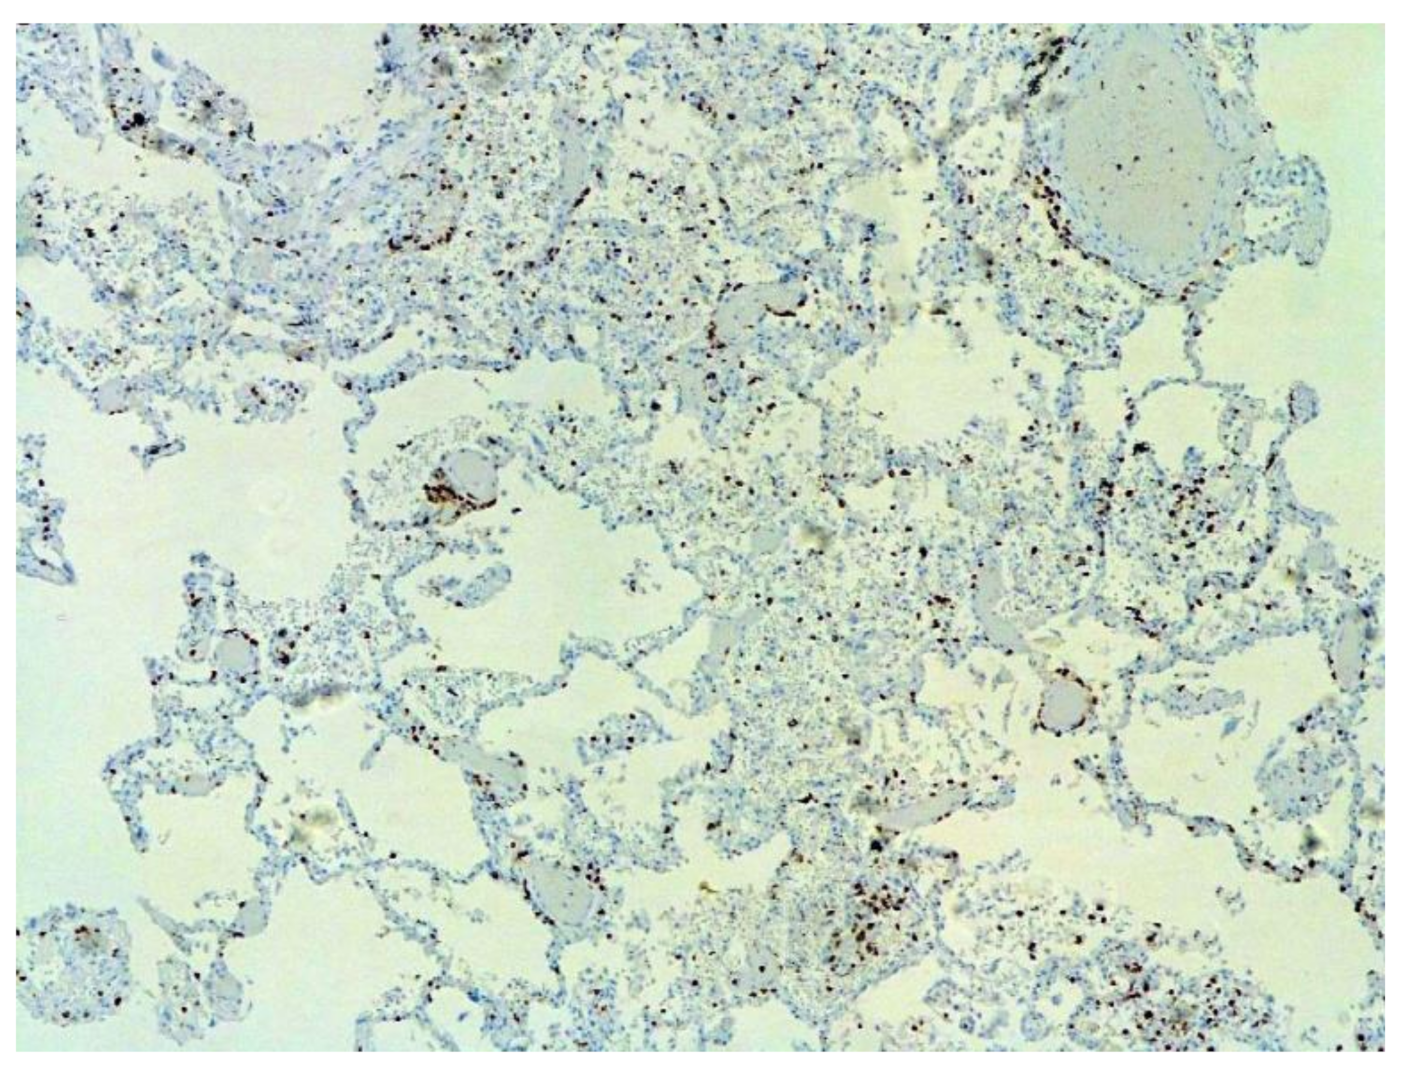

The dynamics of changes in ARDS associated with COVID-19 can only be judged by analogy with SARS and influenza A/H1N1pdm. In the late (productive) stage (after 7–8 days or more from the onset of the disease) of diffuse alveolar damage, macroscopically the lungs are enlarged, low-air, dense, fleshy, and can resemble the density of the liver, sometimes with diffuse whitish layers and areas of different sizes. Microscopically, siderophages, a relatively (in comparison with swine influenza) small number of hyaline membranes (Figure 9), fibrin, squamous metaplasia of the bronchial, and bronchiolar and alveolar epithelium can be detected in the lumens of the alveoli, respiratory and terminal bronchioles, the thickening of the interalveolar septa due to sclerosis, lymphoid (mostly CD3+ and CD 8+) (Figure 10 and Figure 11) and macrophage (Figure 12) infiltration, and the proliferation of type II alveolocytes. The nature of cytoproliferative changes of the epithelium in the trachea and bronchi remains unclear. In the final stage of the disease, sections of fibrous tissue may develop in all parts of the lungs (usually in the lower lobes) (Figure 13), which contributes to the development of chronic respiratory failure. It is notable that near the overgrowth of collagen fibers in the lungs, neoangiogenesis is also typical (Figure 14). The electron microscopic study revealed changed viral particles (Figure 15).

Figure 10.

Numerous CD3+ lymphocytes in lung. IHC ×50.

Figure 11.

CD8+ lymphocytes in lung. IHC ×200.

Figure 12.

CD68+ macrophages in lung. IHC ×200.